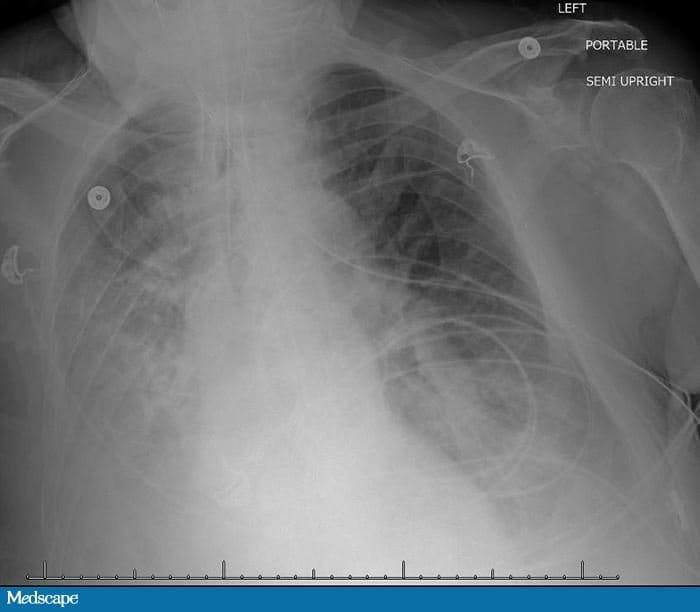

No quarto dia foi iniciado um esquema contendo vancomicina e piperacilina/tazobactam para pneumonia nosocomial. A radiografia de tórax revelou opacidades difusas nas bases pulmonares (Figura 1).